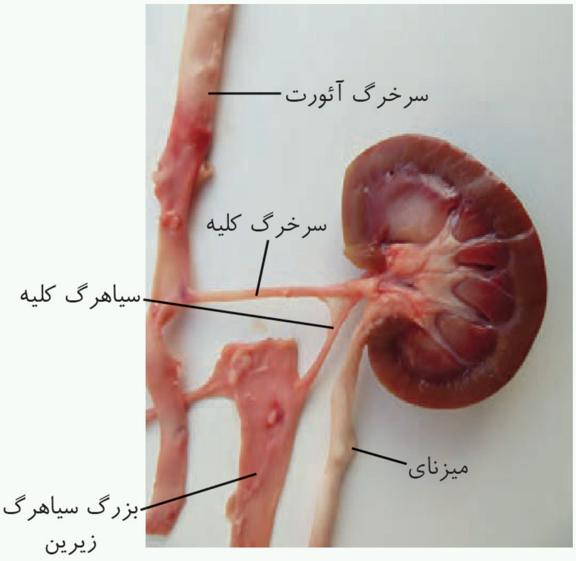

ساختار بیرونی کلیه و حفاظت از آن

کلیهها، اندامهایی لوبیایی شکلاند و به تعداد دو عدد در طرفین ستون مهرهها و پشت محوطۀ شکمی قرار دارند. اندازۀ کلیه در فرد بالغ، تقریباً به اندازۀ مشت بستۀ اوست. به علت موقعیت قرارگیری و شکل کبد، کلیۀ راست قدری پایینتر از کلیه چپ واقع است.

دندهها ازبخشی از کلیه محافظت میکنند. علاوه بر این، پردهای از جنس بافت پیوندی به نام کپسول کلیه، هر کلیه را در بر گرفته است.

سرخرگ کلیه قبل از آن منشعب میشود. انشعابات سیاهرگی بعد از کلیه به هم میپیوندند و سیاهرگ کلیه را میسازند.

ترتیب از بالا به پایین: سرخرگ، سیاهرگ، میزنای.

سیاهرگ کلیه جلوتر از سرخرگ کلیه است.

میزنای از پشت سیاهرگ کلیه عبور میکند.

ساختار درونی کلیه

در برش طولی کلیه، سه بخش مشخص دیده میشود که از بیرون به درون عبارتاند از بخش قشری، بخش مرکزی و لگنچه.

تشریح کلیه گوسفند

بخش قشری کلیه از بخش مرکزی تیرهتر است.

در ناف کلیه چربی وجود دارد.